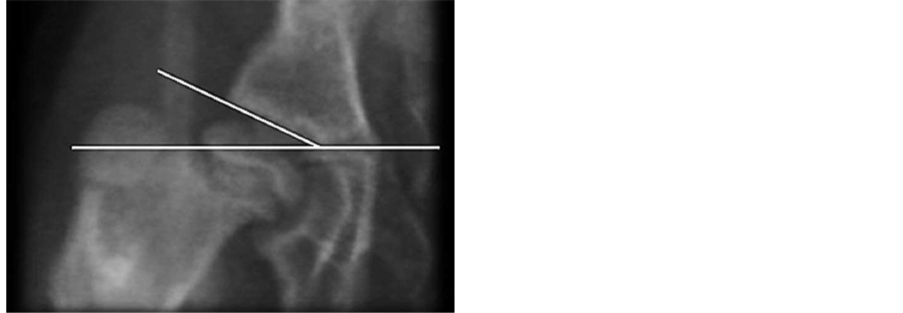

The following parameters were compared between groups: ADI [15] , CE angle of Wiberg, AS and Acetabular anteversion (AA) (Figure 6(a) and Figure 6(b)).

Figure 6. Acetabular antevertion (AA). It’s measured in the true a-p, given by an angle taken from the inferior edge of the acetabulum drawing two vectors which directions are: the first one goes until the medial notch that corresponds to the ending of the anterior wall; the second vector goes until the superior-external edge of the acetabulum (n: 12 degrees). (a) Measured in 3D-CT, (b) Measured in CT scan.